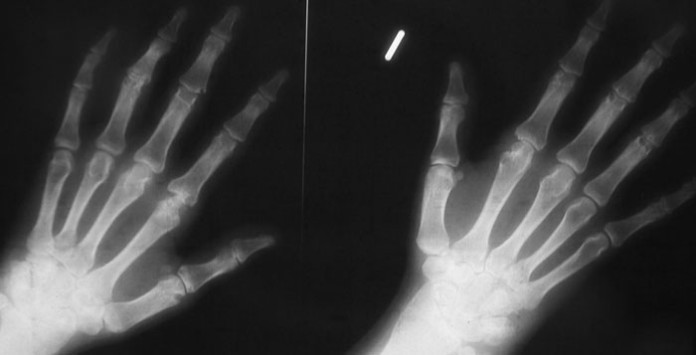

La artritis reumatoide es una enfermedad que causa inflamación dolorosa de varias articulaciones del cuerpo. La cápsula de la articulación se inflama, y la enfermedad también puede destruir el cartílago y el hueso a medida que avanza. La artritis reumatoide afecta a 0,5% a 1% de la población mundial. Hasta este punto, los médicos han utilizado diversos fármacos para desacelerar o detener la progresión de la enfermedad. Pero ahora, investigadores de ETH Zurich han desarrollado una terapia que toma el tratamiento de la artritis reumatoide en ratones a un nuevo nivel: después de recibir la medicación, los investigadores consideran que los animales pueden estar completamente curados.

Los investigadores probaron la nueva molécula de fusión, que se refieren como un «anticuerpo armado’, en un proyecto de CTI junto con la spin-off Philochem ETH. Se utilizó un modelo de ratón en el que los animales desarrollaron, dedos de los pies y las patas inflamadas hinchadas dentro de unos pocos días. Entre otras cosas, los investigadores estudiaron la molécula de fusión en combinación con dexametasona, un fármaco antiinflamatorio similar a la cortisona que ya se utiliza para tratar la artritis reumatoide en los seres humanos. Los investigadores comenzaron a tratar a cada ratón tan pronto como empezaron a mostrar signos de la enfermedad en la forma de las extremidades hinchadas.

Cuando se utiliza por separado, la nueva molécula de fusión y dexametasona sólo lograron frenar la progresión de la enfermedad en los animales afectados. En contraste, los signos típicos de la artritis, tales como dedos de los pies hinchados y patas, desaparecieron por completo dentro de unos pocos días cuando se administraron ambos medicamentos al mismo tiempo. Las concentraciones de toda una serie de mensajeros inmunes en la sangre y el tejido inflamado, que se cambian en la artritis reumatoide, regresaron a sus niveles normales. «En nuestro modelo de ratón, este tratamiento combinado crea una cura a largo plazo», dice Hemmerle, quien, desde que completó su tesis, ha estado trabajando en Philochem, donde continúa el proyecto.